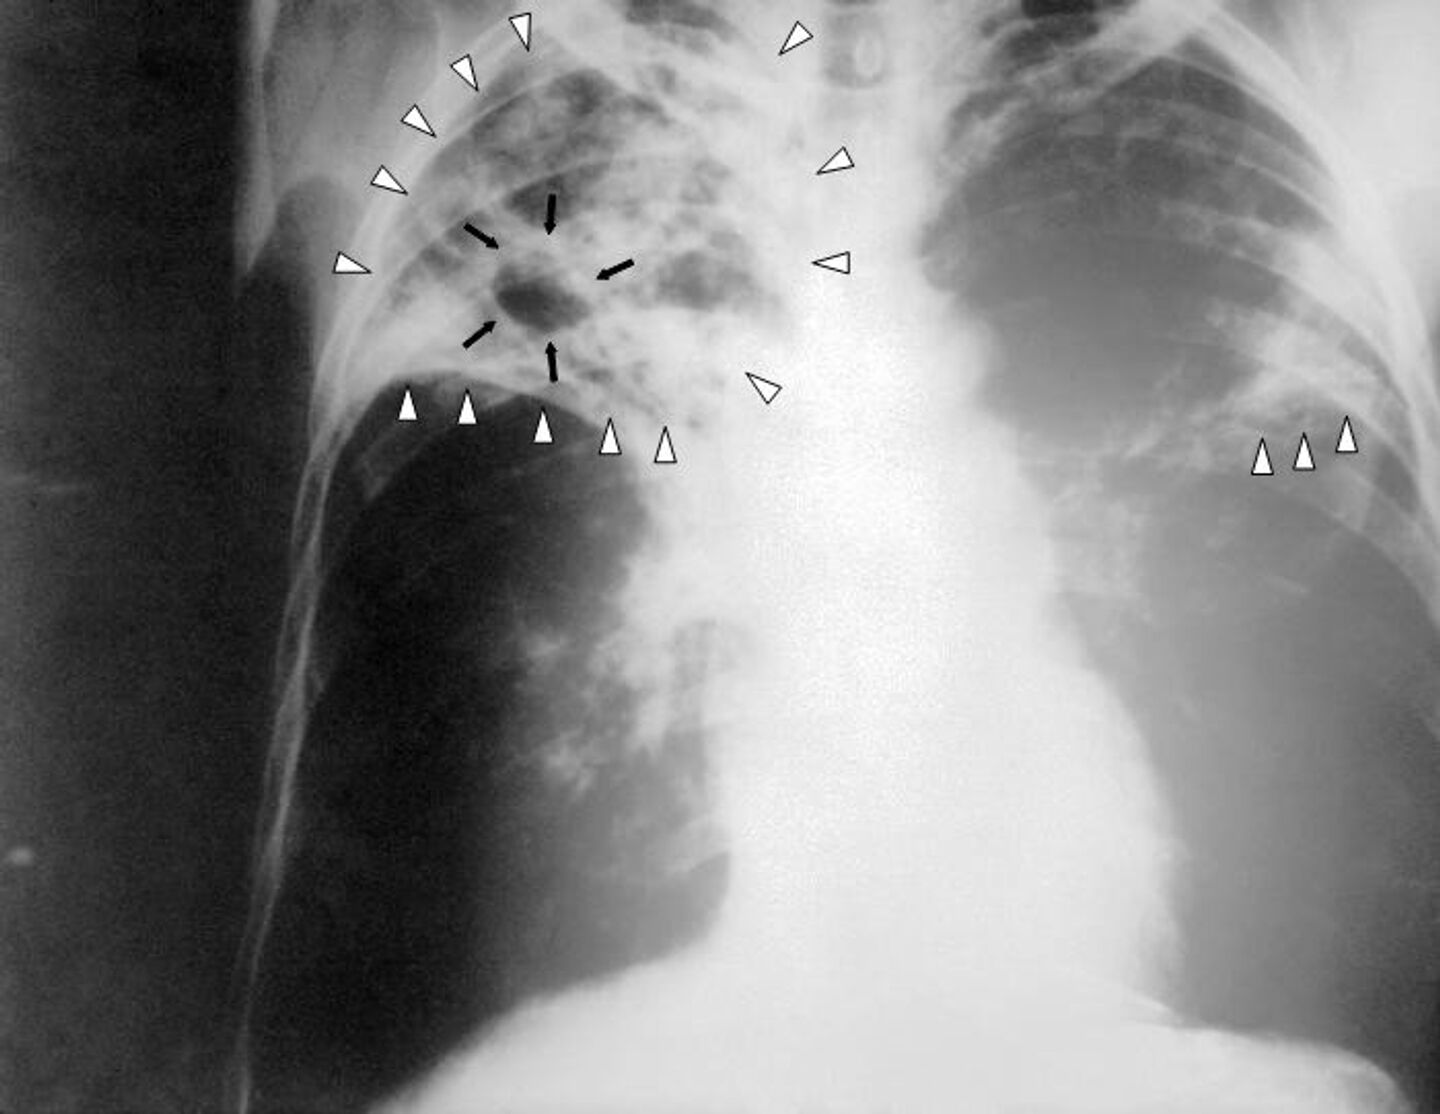

Снимок легких при туберкулезе является важным методом диагностики этого заболевания. На рентгеновских снимках можно увидеть изменения в легких, которые свойственны туберкулезу.

Симптом плакучей ивы туберкулез

Очаг гона на рентгенограмме

Первичный туберкулезный комплекс рентген

Фотографии снимков легких при туберкулезе

В данной статье представлены многочисленные фотографии снимков легких при туберкулезе, чтобы помочь вам понять, как выглядят изменения легких на рентгеновских снимках при этом заболевании.